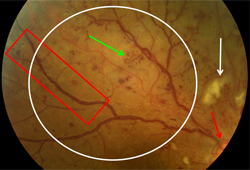

Proliferative diabetic retinopathy: new vessels elsewhere (white arrow), vitreous (intra-gel) haemorrhage (green arrow), retrohyaloid haemorrhage (red arrow)

Courtesy of Moorfields Photographic Archive; used with permission